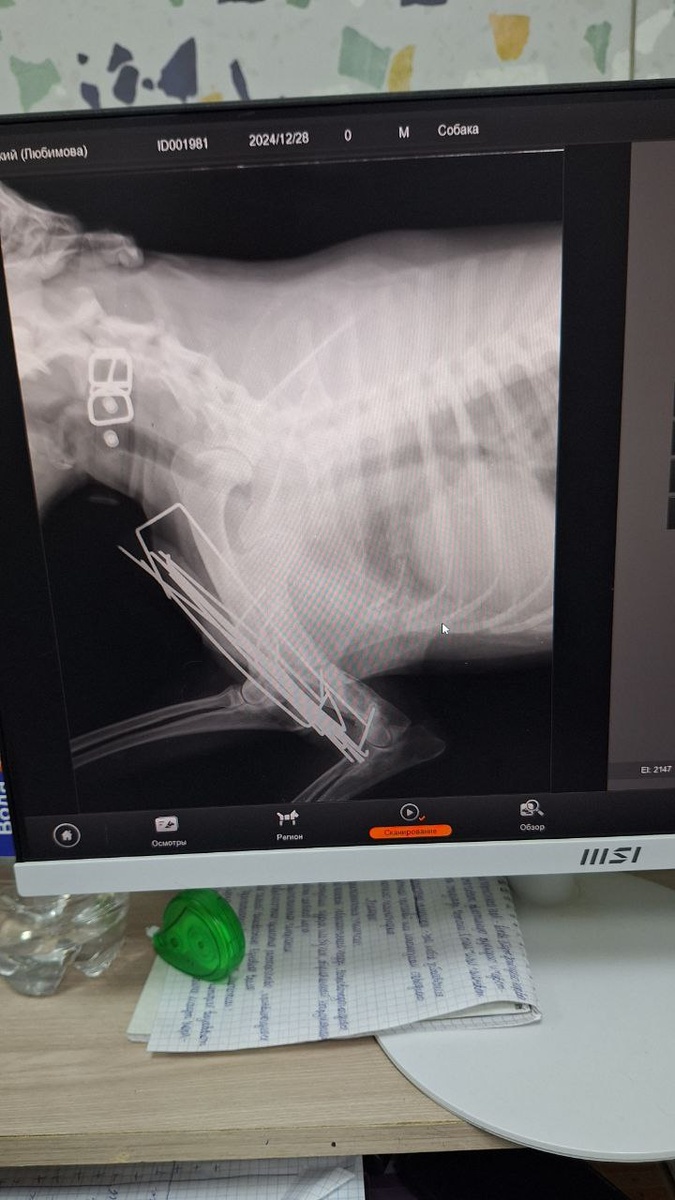

UPD Лео🐕 Сегодня Лео сделали контрольный рентген. Снимать конструкцию ещё не время. Хирург сказал, что плечевая кость срастается долго, поэтому на приём в конце мая😐 Записались на 27 мая. #ПомощьБольнымЩенкам

Сегодня Лео сделали контрольный рентген.

Снимать конструкцию ещё не время.

Хирург сказал, что плечевая кость срастается долго, поэтому на приём в конце мая😐